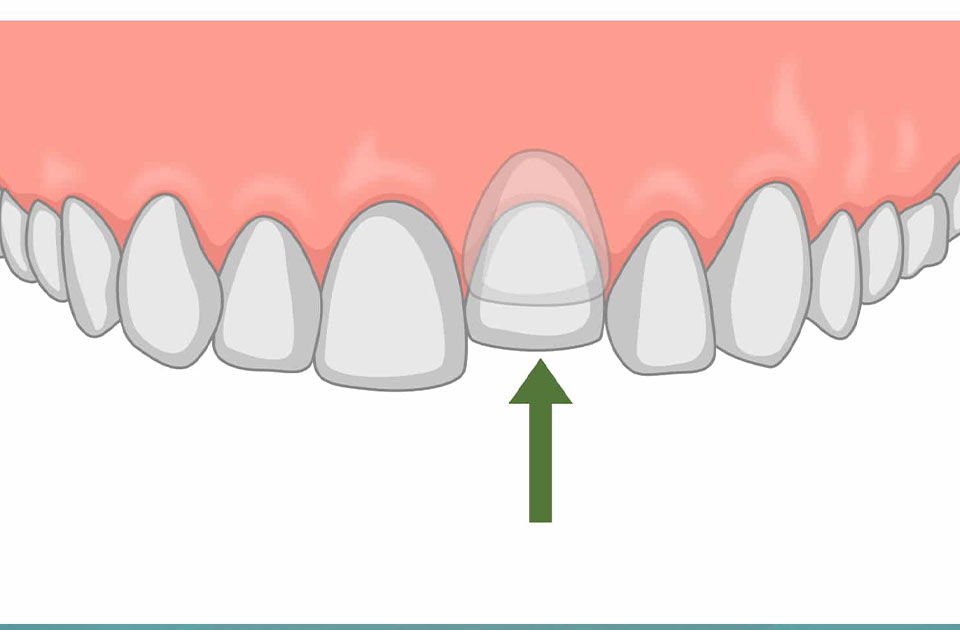

اینتروژن دندان یکی از اختلالات دندانی است که به معنای نفوذ غیرطبیعی یک دندان به داخل استخوان فک می باشد. این وضعیت میتواند ناشی از عوامل مختلفی از جمله ناهنجاریهای ارثی، آسیبهای فیزیکی یا مشکلات ارتودنسی باشد که امروز با هم به درمان این مشکل می پردازیم .

اینتروژن دندان نه تنها بر زیبایی ظاهری فرد تأثیر می گذارد بلکه می تواند منجر به مشکلات جدی تری در سلامت دهان و دندان گردد.